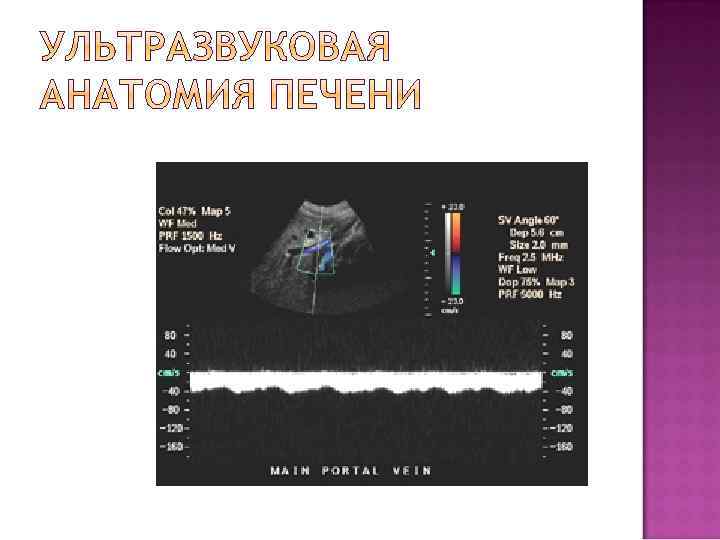

Доплерографическая картина нормального кровотока в портальной вене, который характеризуется постоянной скоростью, без систолодиастолической разницы спектра